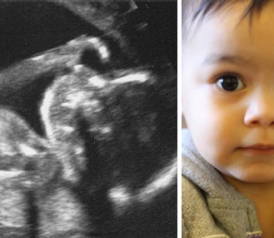

It is not surprising, therefore, that questions about consciousness lie at the heart of many of our most fundamental ethical debates, one of which is abortion and the right to life. This is an appropriate point for me to play my proud father card and slip in a couple of pictures of my daughter, Lalana. The ultrasound was taken halfway through pregnancy, at 20 weeks. Soon after this scan, we could clearly feel her kicking.

The second image is a recent photo of her. As a 2-year-old, Lalana runs around everywhere and has a vocabulary of a few hundred words. She can convey events to us that happened days or weeks before, usually because she is still so excited about them. She can also store wishes for the future. For instance, we might tell her offhand that when we get home, we’ll play with making bubbles. Hours later, as soon as she enters the house, she’ll run straight to the shelf with the bubble bottle and scream, “Bubbu! Bubbu!” She has a strong set of loves and hates, and her emotionally sensitive, passionate, cheeky, disturbingly stubborn personality is already pronounced.

Having prided myself on my objectivity throughout my adult life, I’ve embarrassingly found that my daughter is the main exception to this aim: I’ve not only been taken aback by how fiercely I love her but also by how proud I am of her and how quickly I distort the truth to make her seem exceptional in every way. But when I can step back from these views, I ask myself: At what point did she become conscious? Obviously she is conscious now, as she can tell me her inner thoughts via language. But when did she start experiencing her environment? On a personal, intuitive level, I had little doubt that her first intense bursts of laughter at my silly antics, when she was a few months old, reflected a substantive consciousness. But was she conscious well before this? Was she aware when she was still in the womb, kicking away? Or could she only experience things when she first opened her eyes to the outside world on the day of her birth?